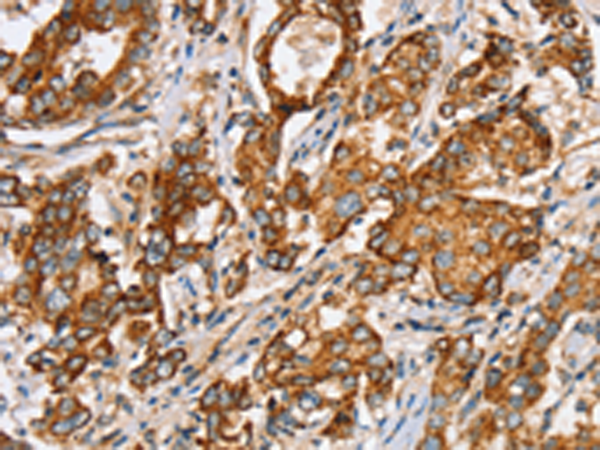

分类: 科研抗体货号: P12173别名:应用: IHC反应种属: Human, Mouse